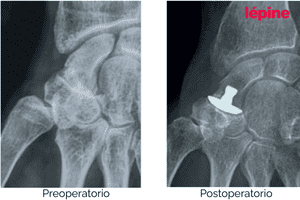

Casos clínicos: antes y después del tratamiento

Las siguientes imágenes muestran casos clínicos reales que ilustran la evolución del paciente antes y después del tratamiento con implantes ortopédicos de mano.

Estos resultados reflejan el objetivo principal de nuestras soluciones: restaurar la función, reducir el dolor y mejorar la calidad de vida, siempre mediante evaluación y seguimiento médico especializado.